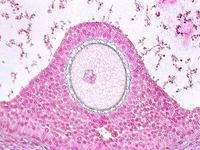

After ovulation, the uterine lining becomes more tortuous. The lining is now under the control of progesterone. This steroid hormone stimulates the lining to secrete material that may help nourish both sperm and a potential pregnancy. The glands expand and the lumina are wide and contain products of secretion. The glandular epithelium may be characterized by a droplet of secretory material under the nucleus (near the base) about 2 days after ovulation (day 16). Then, the secretory products move more towards the lumen. Slide 87 shows the Secretory phase of the uterine lining. Note the sections showing coiled or tortuous glands and the dense lamina propria.

Which cells secrete the progesterone during the uterine secretory phase?